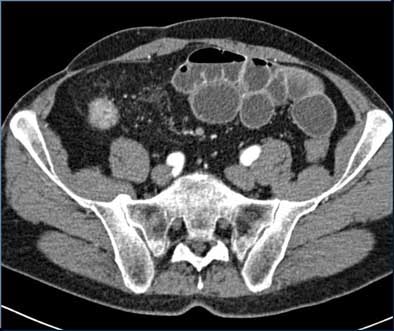

![]() |

| Top and below: In same 21-year-old patient, axial CT enteroclysis shows long-segment inflammatory reaction and severe thickening of the terminal and preterminal ileum due to histologically proven Crohn's disease. Bottom image, equivalent coronal multiplanar reformation. |